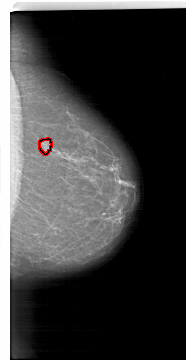

A_1718_1.RIGHT_CC

RIGHT_CC LINES 6481 PIXELS_PER_LINE 3346 BITS_PER_PIXEL 12 RESOLUTION 43.5 OVERLAY

FILE: A_1718_1.RIGHT_CC.OVERLAY

TOTAL_ABNORMALITIES 1

ABNORMALITY 1

LESION_TYPE MASS SHAPE FOCAL_ASYMMETRIC_DENSITY MARGINS ILL_DEFINED

ASSESSMENT 4

SUBTLETY 4

PATHOLOGY BENIGN

TOTAL_OUTLINES 1

BOUNDARY